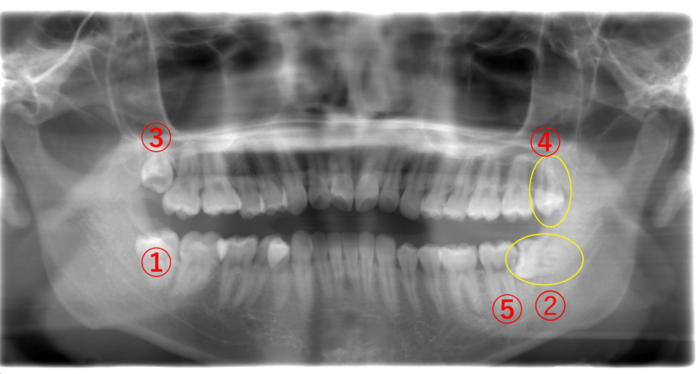

(45歳男性)

| 年齢・性別 | 45歳・男性 |

|---|---|

| 主訴 | 最近、奥さまより口臭を指摘されるようになった。自分でも違和感がある。 |

| 歯ブラシ | 奥まで磨けていない。お口の中に汚れが結構残っている。 このままでは親知らずだけではなく、他の歯が虫歯になる可能性が高い。 |

画像①の親知らずが真横に生えていて、手前の⑤の歯との間に隙間があります。ここに食べかすが入り込むとどんなに歯を磨いても取れません。取り除かれない食べかすが腐り、口臭の原因となっていると思われます。

早めに抜くことで口臭はなくなると思われます。また➁の親知らずも汚れが溜まりやすそうなので、口臭の原因となる可能性があります。

そして、③の親知らずは、黒く透けていることからして虫歯になっています。

このことから、歯ブラシが親知らずの奥まで十分に届いていないことが考えられます。

とはいえ、親知らずまでしっかりと磨こうとすれば嘔吐反射や隙間の問題もあり、なかなかパーフェクトに磨くのは難しいと思います。

この場合、右側上下(①と③)と②の親知らずを抜くことをオススメします。

④の親知らずは、歯ぐきが被ったまま出てこないのであれば積極的に抜かず様子を見ても良いですし、もし全部抜いてスッキリしたいのであれば、抜いた方が良いと思います。

口臭が気になるときは、歯科医院で診てもらいましょう。